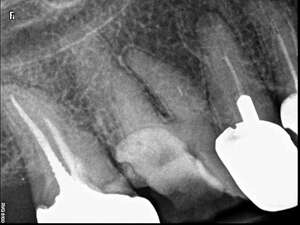

Avant